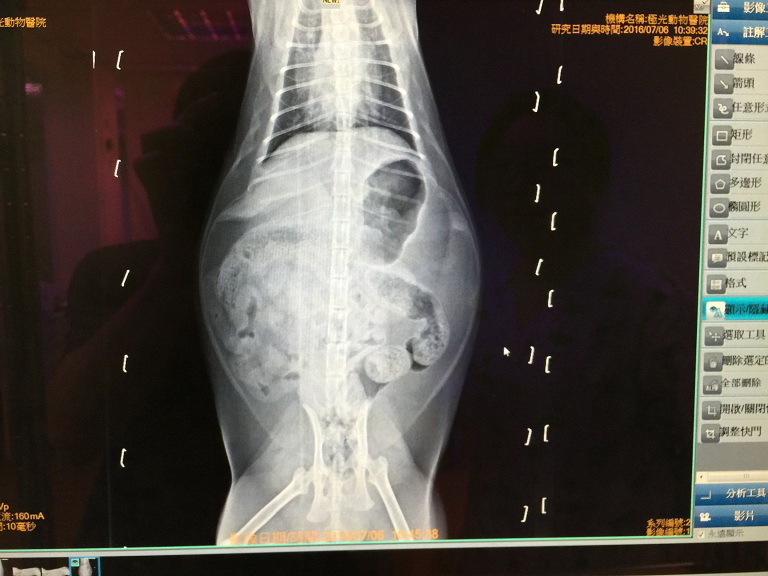

7/6 極光回診- 小樹

小樹最近的病症有3個- 1. 脹氣 2. 咳嗽 3. 下巴粉刺

X光照片中可看到胃和腸道裡面有不少氣體,

醫生認為可能有不好的細菌在腸道內孳生,

可每天吃一次腸寶 (益生菌) 試著改善菌叢生態、持續吃一個月。

醫生說小樹的支氣管發炎,

導致出現咳嗽次數頻繁的情況,

需要每天早晚噴霧才會改善。

7/20 極光回診:小樹- 6.36kg

醫生在看過小樹的X光片之後,

認為小樹的肺部已經沒有之前那麼混濁的樣子,

且在持續每天吃腸寶之後,

肚子脹氣的大肚子也消了非常多。

因此早晚噴霧可改為只加20cc食鹽水即可、不需噴霧藥劑,

醫生也想看看在沒有加入調配藥劑的情況下的治療效果。